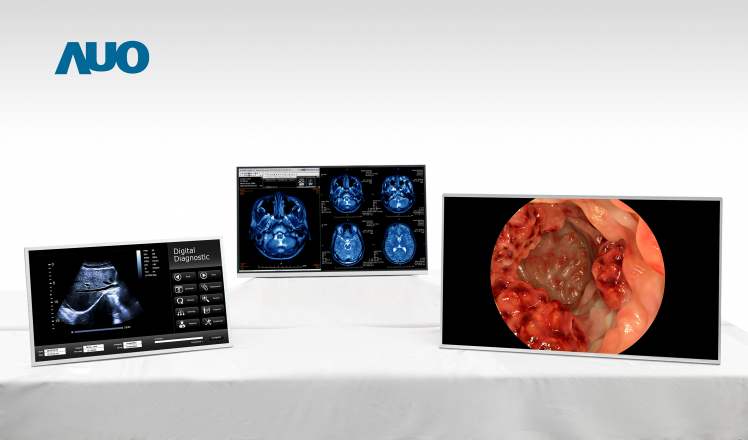

High Resolution, High Contrast, and Wide Color Gamut Medical Displays Present Detailed and Accurate Images

AUO’s series medical displays with high resolution, high contrast and wide color gamut |